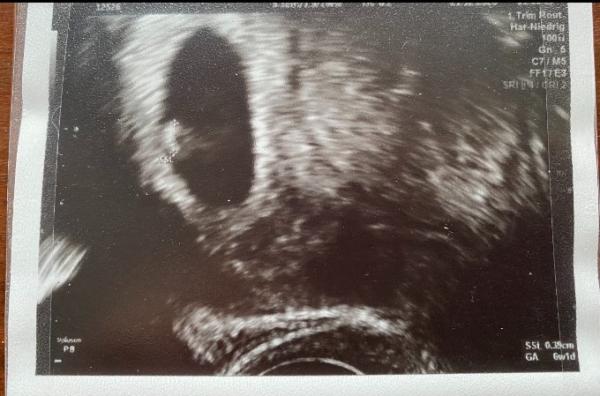

wer kennt diese Methode? es wurde bei mir vaginal geschallt:) was dennt ihr was es wird bin gespannt

Bild zu RAMZI Methode Junge oder Mädchen - Schwanger - wer noch? Rund um die Schwangerschaft

Laut Ranzig.methode geht es doch darum wo die Plazenta sitzt,bei vaginalen Ultraschall sind die Bilder spiegelverkehrt, allerdings weiß ich Grad aus dem Kopf nicht welche Seite was sein soll Bei uns hat das so ziemlich nie gepasst,weder die Theorien,noch der chinesische Kalender,und schon gar nicht Bauchform und Symptome,danach hätte ich einen Jungen,ein Mädchen,Zwillinge und ein Alien,ich bekomme aber unser 4.Mädchen

irgendwie sagt jeder was anderes in der vaginalen Ultraschalluntersuchung soll es genau so sein wie auf dem Bild und wenn es vom Bauch geschallt wird dann spiegelverkehrt